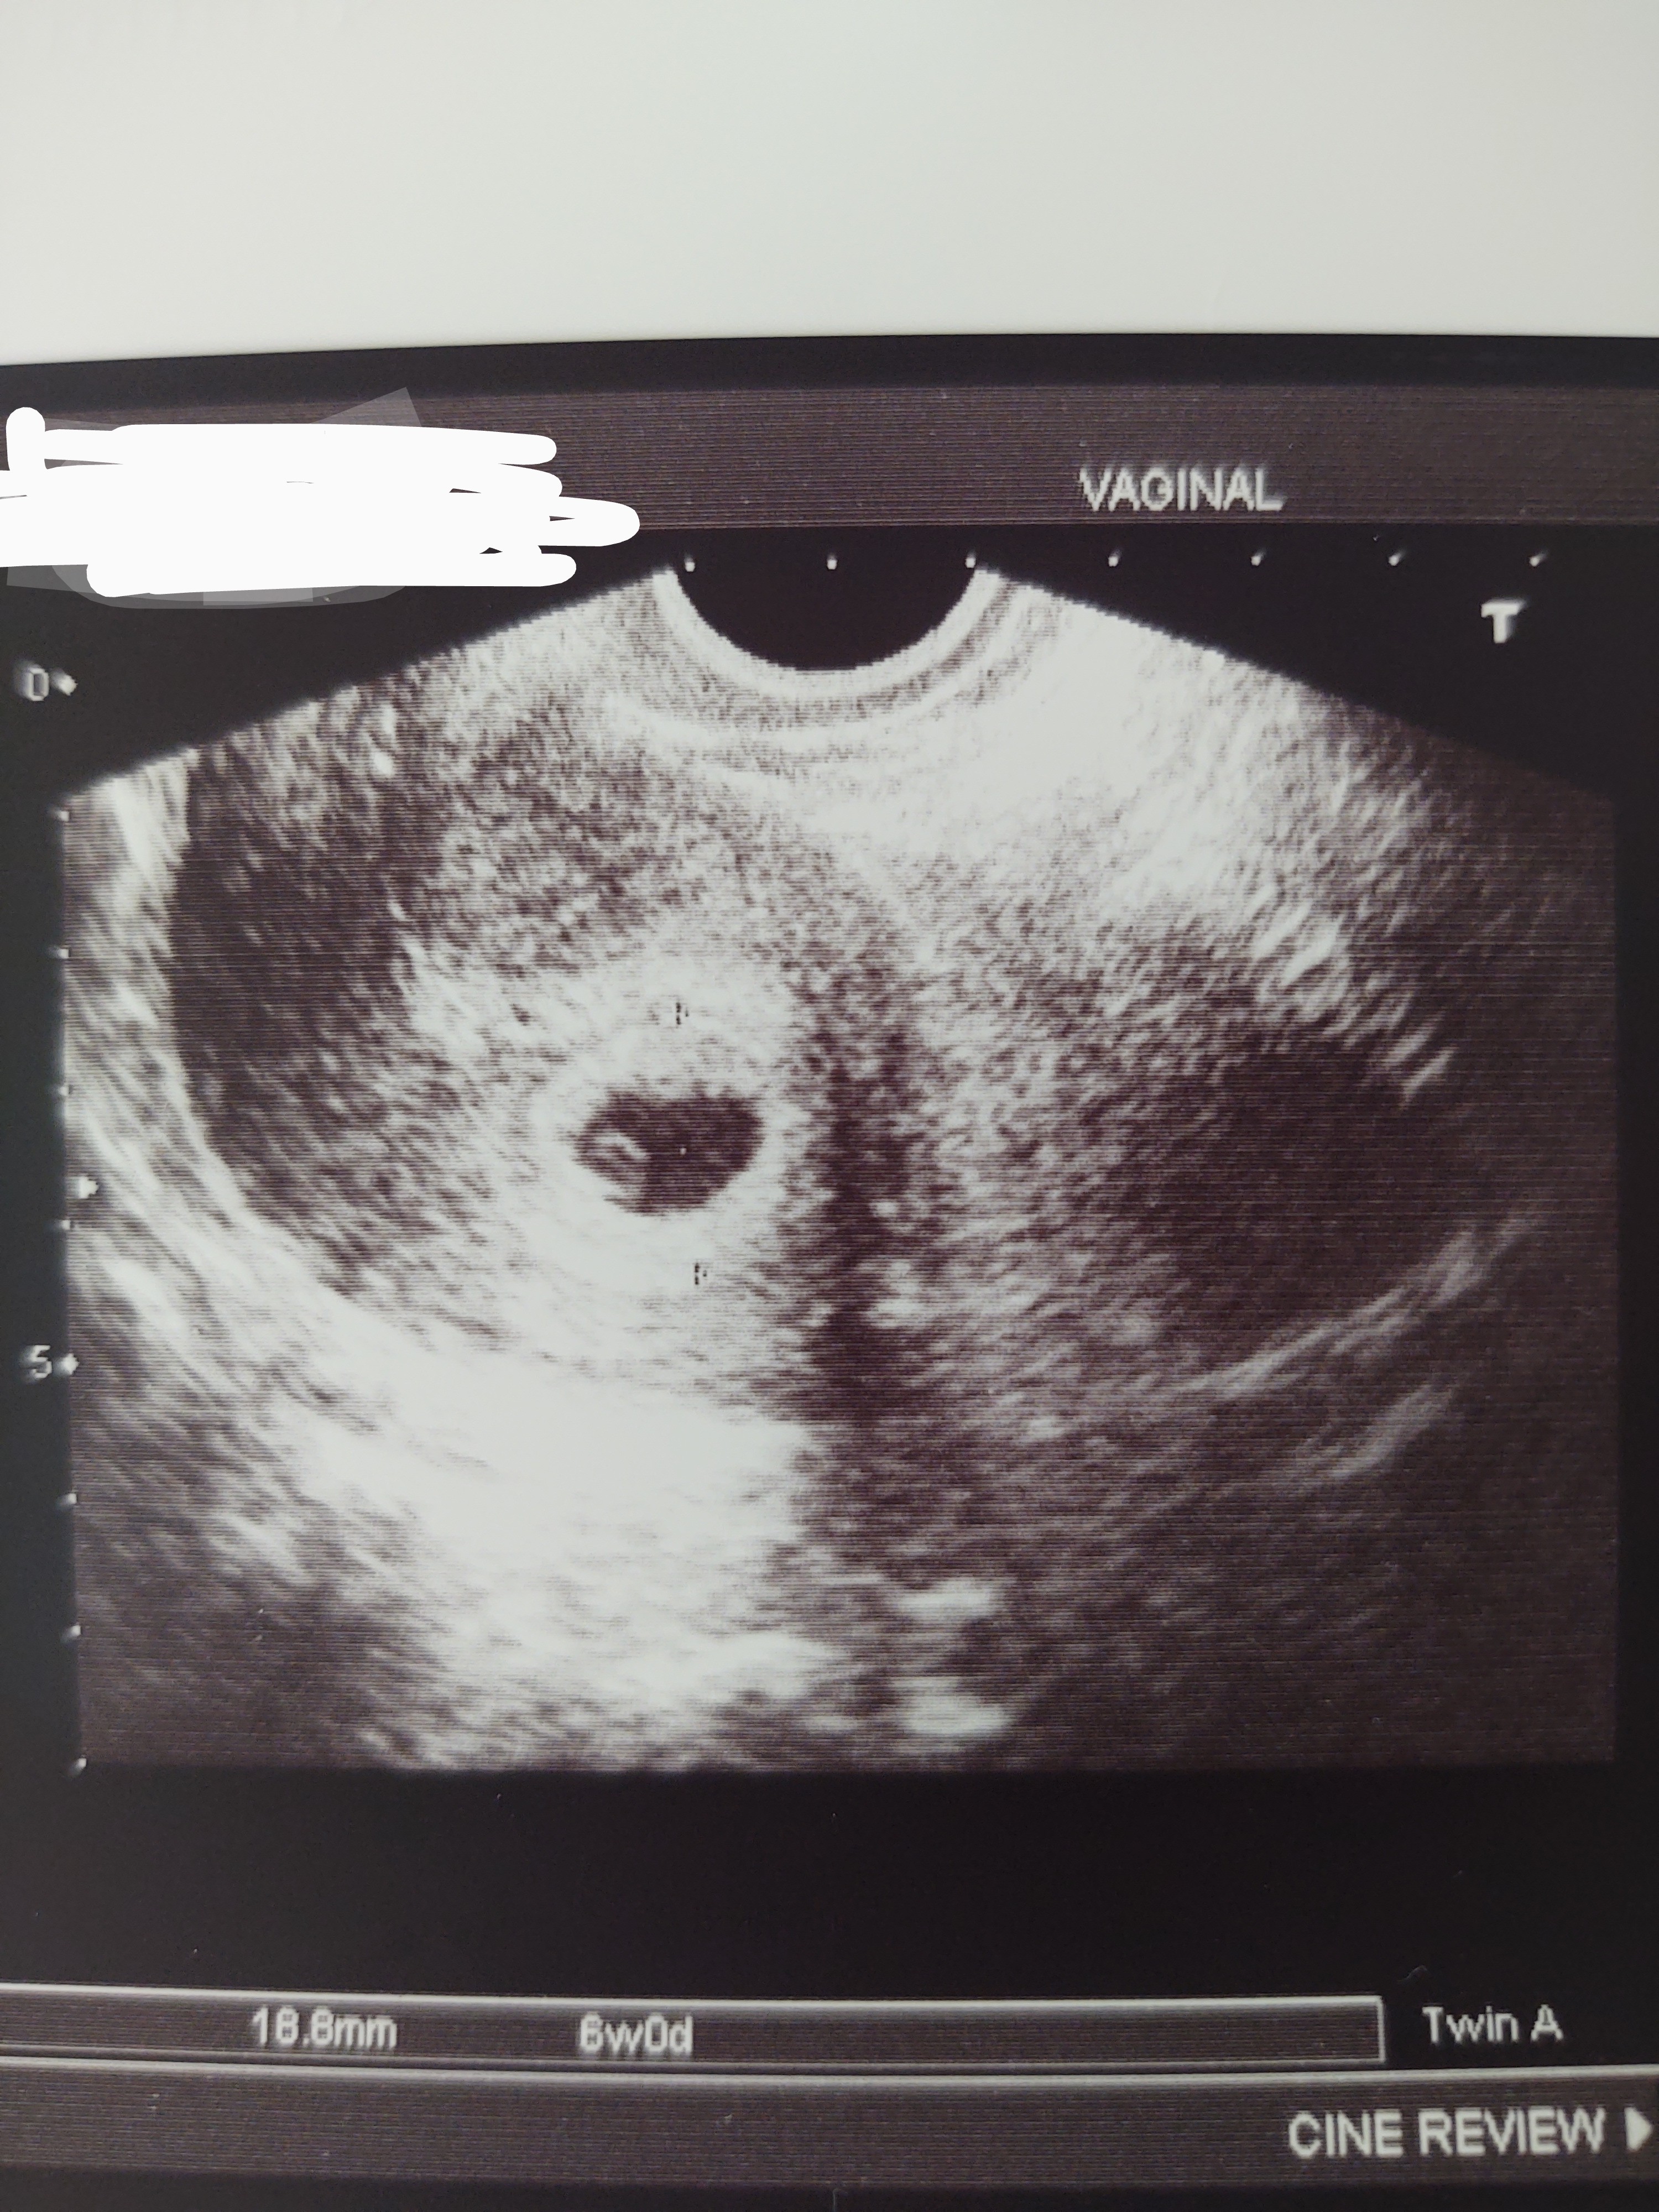

Uf jestem po wizycie. Ciąża wychodzi 5 dni młodsza ale na ten moment wszystko jest ok😊 TP 01.04.2022 więc miałam rację zostając z Wami😁😍

Załączniki

• IMG_20210809_124131332~2.jpg

IMG_20210809_124131332~2.jpg

1,9 MB · Wyświetleń: 101